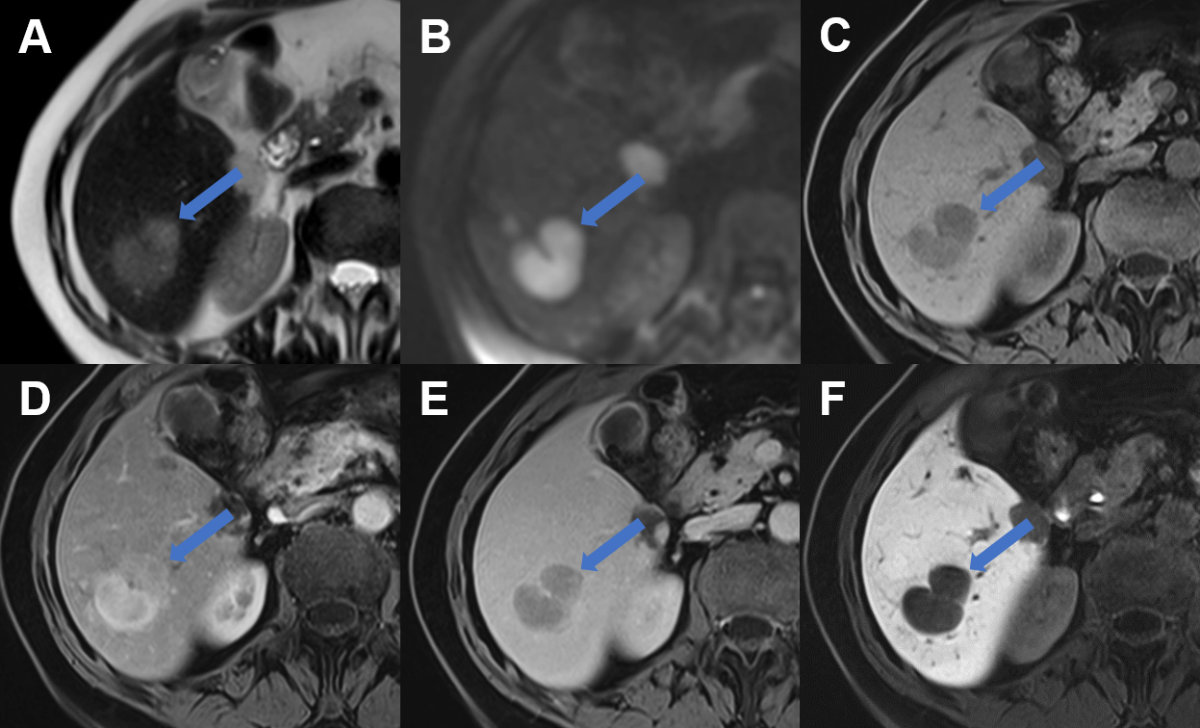

Figure 9Hepatic echinococcosis on CT and MRI. A T2w axial MRI, B T1w fs axial image after gadolinium based i.v. contrast and C CT image after iodine based i.v. contrast in a 37-year-old male patient with cystic echinococcosis (E. granulosus) demonstrating two lesions: the anterior with heterogenous signal on T2w, lack of enhancement and coarse calcifications visualized on CT (arrow, CE5). The posterior lesion with hyperintense detached membrane on T2w, lack of enhancement and faint visibility of the membrane on CT (arrowhead, CE3). D T2w axial MRI, E T1w fs axial image after gadolinium based i.v. contrast and F CT image after iodine based i.v. contrast in a 74-year-old male patient with alveolar echinococcosis (E. mulitlocularis) with pathognomonic microcystic features on T2w image and partial necrosis, infiltrative aspect and coarse calcifications seen on CT.

MRI is also the second imaging modality of choice for alveolar echinococcosis after conventional ultrasound. On MRI, microcystic, alveolar structures are a pathognomonic feature of alveolar echinococcosis (figure 9). However, many lesions are atypical and of an infiltrative character. For detection of calcifications and in patients incompatible with MRI, CT usually has a role. On CT images, alveolar echinococcosis presents as mixed hyperdense-hypodense lesions with possible necroses.